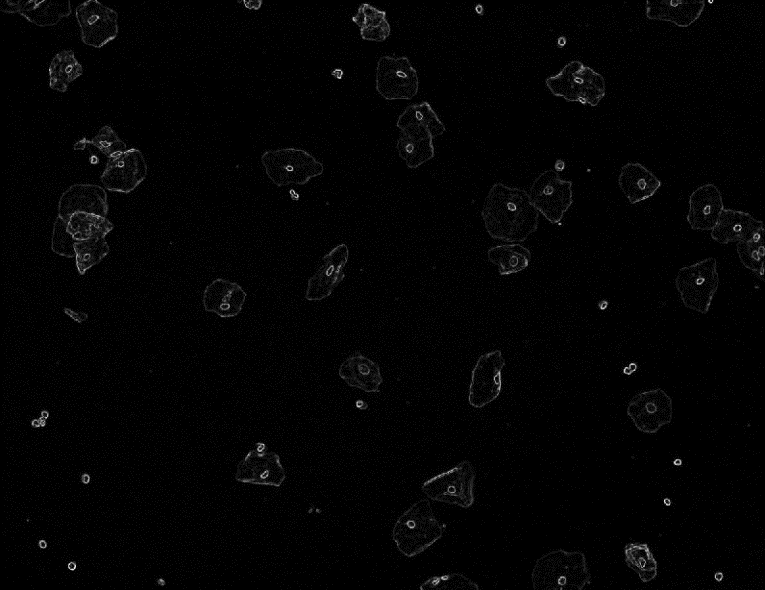

本文结合了宫颈细胞病理学理论基础,以宫颈细胞涂片图像的分割,特征参数提取为目标,使用图像处理等技术,对宫颈细胞图像的分割技术,特征参数的计算和提取进行了系统研究,并完成了相应的系统实现。主要包括:(1)针对Otsu法对宫颈细胞图像分割的精度不够高和效率低等问题,采用基于图像色彩变换,滤波去燥,形态学重构等方法对细胞图像进行预处理,提高分割的准确性;(2)在Otsu法粗分割出细胞质和细胞核的基础上,使用基于局部最小值的改进的分水岭方法进行单细胞的精确分割和重叠细胞质的分割,根据宫颈细胞质和细胞核的定位区分出杂质和细胞;(3)在宫颈细胞图像特征定量分析方面,在处理后的图像上提取了有效的形态学和纹理特征,包括细胞核圆形度、细核面积、核长宽比、胞浆比、粗糙度等。

本文提出的方法,与传统的分水岭算法相比,显著抑制了过分割现象,对于边缘清晰的单细胞和重叠后不太模糊的细胞团,分割效果较理想,显著提高了分割算法的精度。

This article combines the theoretical basis of cervical cytopathology, using cervical smear image segmentation, feature parameter extraction as the goal, and using image processing techniques to systematically study cervical cell image segmentation techniques, feature parameters calculation and extraction. And implement the corresponding system. The main contents are as follows:(1) For the problems of Otsu's method on the accuracy of image segmentation of cervical cells is not high enough and the efficiency is low, such methods as image color transformation, filtering and desiccation, morphological reconstruction are used to preprocess the cell image and improve segmentation accuracy; (2) On the basis of coarse segmentation of cytoplasm and nucleus by Otsu method, an improved single-cell segmentation and overlapping cytoplasm segmentation were performed using an improved watershed method based on local minima, and distinguish impurities and cells based on the location of cervical cytoplasm and nuclei; (3) In the quantitative analysis of image characteristics of cervical cells, effective morphological and texture features were extracted on the processed images, including circularity of nuclei, area of nuclei, ratio of nuclear to aspect ratio, and cytoplasm ratio, roughness, etc.

The proposed method, compared with the traditional watershed algorithm, significantly suppresses the over-segmentation phenomenon. The segmentation effect is ideal for single-cells with clear edges and overlapping cell cluster with clear contour, which significantly improves the accuracy of the segmentation algorithm.

第三章根据宫颈细胞图像中细胞核和质颜色,形态特点,提出了几种分割方法,包括对宫颈细胞图像的粗分割,ROI区域提取,基于Otsu和改进分水岭的重叠宫颈细胞图像的分离方法,并对相关方法进行模拟和实验验证。